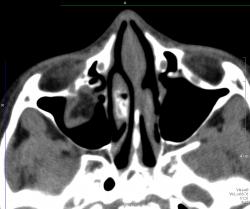

Отломок напоминает открытую дверцу, в которую вываливается нижняя прямая мышца и клетчатка. Бывает, что такая "дверца" захлопывается и ущемляет содержимое орбиты. Тут нужен зоркий глаз и знание клиники, так как сам перелом можно уже и не увидеть, отломок встал на место.

Глазное яблоко, стало быть, уцелело? Что же пролабирует в верхнечелюстную пазуху?

Зрение в порядке за исключением "пустяка" диплопии. Почему называется взрывным переломом? Вероятно потому, что перелом не от прямого удара по кости, иначе ломался бы край орибы. Ломается тонкое место в дне орбиты от резко повышения давления в орбите в результате прямого удара. Американцы приводят как пример типичный механизм прямого удара бейсбольным мячом. Как ни странно, медиальная стенка ломается реже, и еще реже верхняя стенка.

Следовательно, с учетом комментария Петровича, в гайморову полость пролабируют мышцы и клетчатка?

Вы правы, Валентин Львович, этот червячок на фоне темной жировой клетчатки орбиты нижняя прямая мышца. А в левой гайморовой пазухе случайная находка, видимо полип, клиники нет.

У меня тоже два случая подряд прошли недавно. Оба - нижняя стенка. В одном случае - с гемосинусом, в другом - без. На рутинных рентгенограммах переломчики не видны, но если учитывая клинику присмотреться, то мы увидим мягкотканную тень ущемленной клетчатки свисающей в гайморовую пазуху. Взрывной перелом получается, если предмет, ударивший по глазу, больше по размерам диаметра орбиты. У нас в одном случае -коленка соседа, в другом - кулак)))